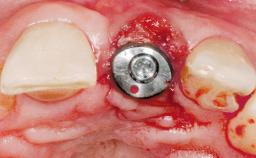

A 30-year-old female patient had lost tooth 21 and was referred to our clinic for consultation and treatment. Due to advanced apical infection, tooth 21 had been extracted two months earlier at another clinic and an acrylic-resin tooth had been bonded to the adjacent teeth. The patient desired implant treatment to avoid any damage to the adjacent natural teeth. While the patient had no history of any systemic disorder, she was a heavy smoker and exhibited medium to advanced periodontitis in the entire jaw. After the initial treatment to achieve a pocket probing depth of less than 4 mm and no bleeding on probing, a decrease in the height of the papillae mesial and distal to the extraction site and overall gingival recession were observed.

Type of Implants One-Piece|Reduced-Diameter

Attachment One-Piece|Reduced-Diameter

Placement Protocol Early or late implant placement

Bone Volume Deficient horizontally, requiring prior grafting